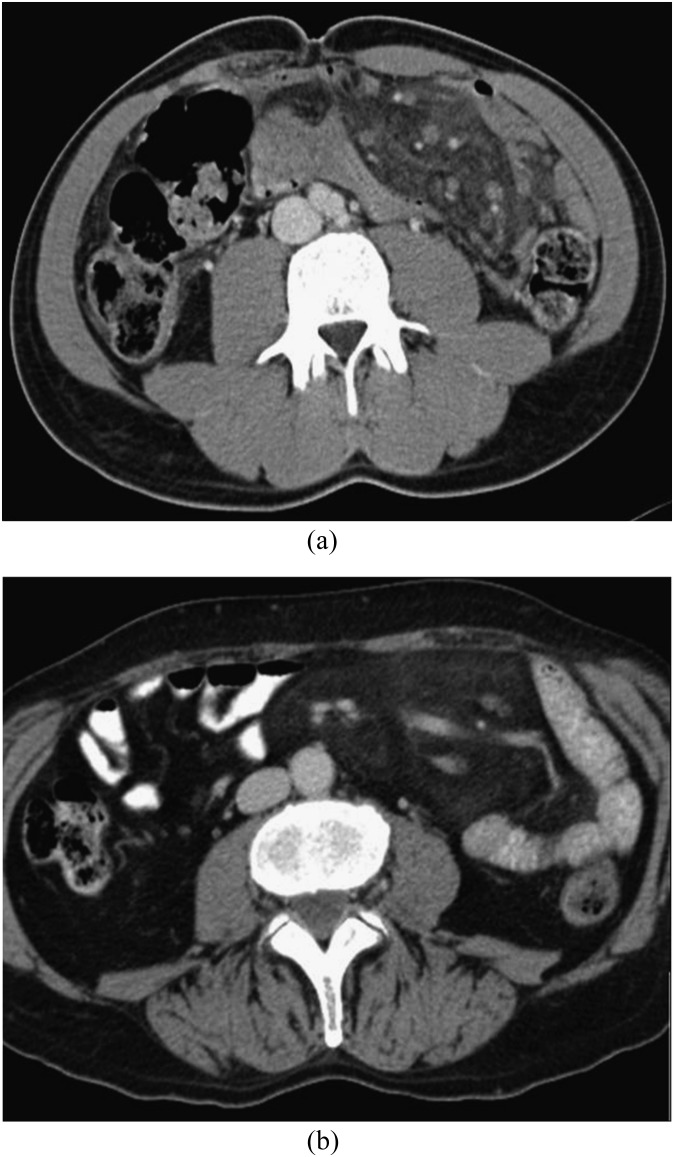

Figure 1 shows two examples of MP. CT findings are summarized in Table 4. Mean maximum transverse diameter was 9.5 cm. The maximum transverse diameter of the mass was directed towards the left abdomen (leftward orientation) in the majority of patients.13 The “fat-ring” sign (Figure 2) was present in most patients. Mean density of the fatty halo around the mesenteric vessels and nodules or lymph nodes was significantly lower than the density of the mass (Table 4). In more than half of patients, a “tumoural pseudo-capsule” was positive (Figure 3). Nodules of soft-tissue density were found in 92 patients, calcifications only in 4 patients.

Figure 1.

(a, b) Mesenteric panniculitis: the mesenteric fat is hyperdense compared with the subcutaneous or retroperitoneal fat and displaces the surrounding small bowel loops.